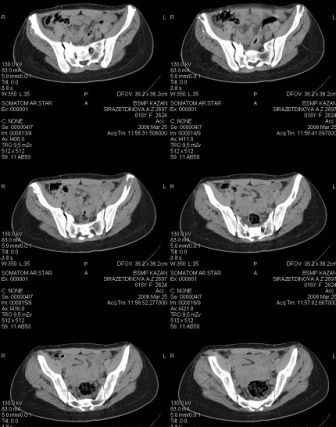

Уважаемые коллеги! Девушка 18л сросшиеся переломы лонных, седалищных костей с обеих сторон, перелом крестца справа,перелом костей голени справа (зио), 3 мес после травмы, АВФ снят с таза.

Патологической подвижности нет. Стоит самостоятельно, ходит с костылями, поскольку 3 месяца практически не ходила. Беспокоит выступание лонной кости в области лобка, хотя объективно грубого косметического дефекта нет. На кт разворот лонной кости в сагиттальную плоскость. Вопрос: стоит ли добиватьсяполной репозиции или же достаточно произвести остеотомию верхушки выступающего отломка?

Для уточнения диагноза ниеобходимы обзорные рентгенограммы таза (прямая и inlet), Кт срезы на уровне переломов для определения степени сращения и решения вопроса о методе оперативного восстановления анатомии (делать ли остеотомию, низводить ли задние отделы), ни о какой "остеотомии выступающих отломков" тем более у девочки 18 лет речи быть не может.

Предоставляю срезы. Если пациентку функционально ничего не беспокоит, стоит ли навязывать ей лечение.